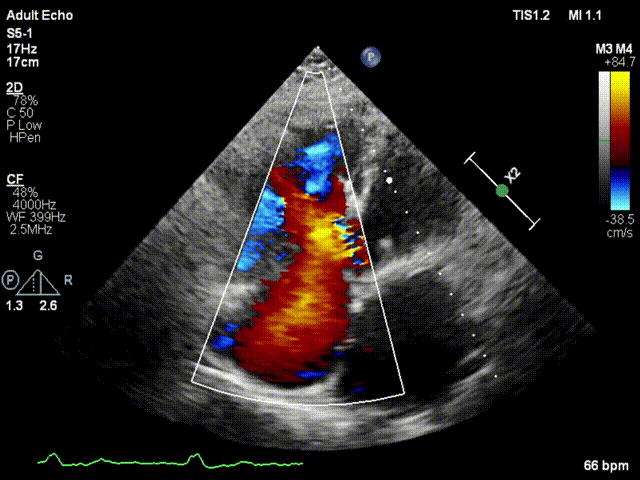

本次接受治療的患者是一名74歲的女性,14年前因風(fēng)濕性心臟病行二尖瓣生物瓣植入術(shù),合并房顫。近3年來反復(fù)因腹脹、納差、下肢水腫入院,藥物治療欠佳。心臟超聲顯示三尖瓣極重度反流(有效反流口面積:0.76cm²,反流容積:79ml),繼發(fā)性右房室增大及上、下腔靜脈增寬(右房上下徑*左右徑:52*41mm,右室左右徑:46mm,下腔靜脈:29mm),右室收縮功能正常,肺動脈收縮壓 43mmHg,左心室射血分?jǐn)?shù)73% 。患者既往開胸手術(shù)史,術(shù)前評估STS 評分為7.02分,CRS 9分,無法接受體外循環(huán)下三尖瓣外科手術(shù)。面對這一傳統(tǒng)治療無法解決的困境,葛均波院士及其團隊周達新教授、潘文志教授、張源博士、陳莎莎博士及心超室的潘翠珍教授、李偉教授經(jīng)過討論決定,采用創(chuàng)新的Lux-Valve Plus系統(tǒng)為患者進行經(jīng)血管三尖瓣置換。

手術(shù)在患者全麻狀態(tài)下進行,采用經(jīng)右側(cè)頸靜脈作為入路,將裝載有人工瓣膜的輸送器緩慢推送至右心房;并在經(jīng)食道超聲和DSA的引導(dǎo)下小心調(diào)整輸送器角度,將輸送器送入右心室;逐步釋放瓣膜錨定裝置和盤片,調(diào)整瓣膜位置后,錨定瓣膜完成植入。術(shù)后右房壓明顯下降,從術(shù)前的25/10(16) mmHg降至術(shù)后即刻的12/7(10) mmHg,術(shù)后超聲提示人工三尖瓣同軸性良好,固定牢固,無反流及瓣周漏,手術(shù)室即刻拔除氣管插管。